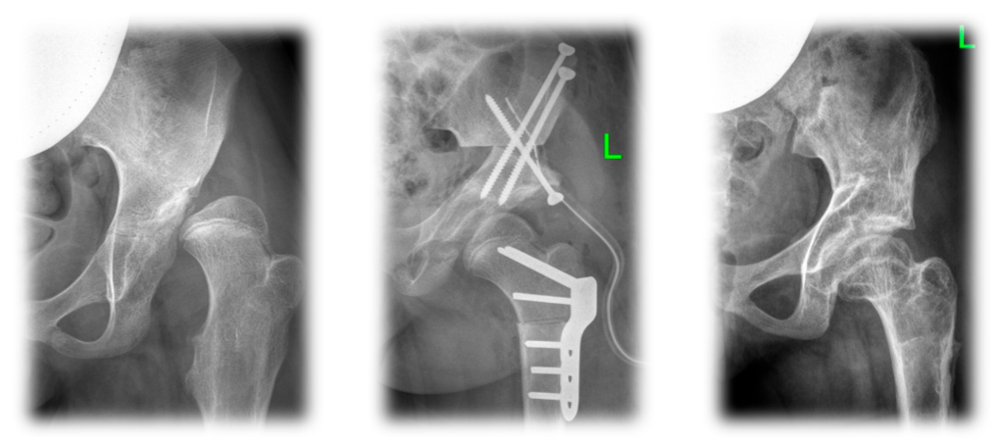

Диагностика ТБС рентгеном и асептический некроз: особенности лечения

Раздел: Снимки-откровения